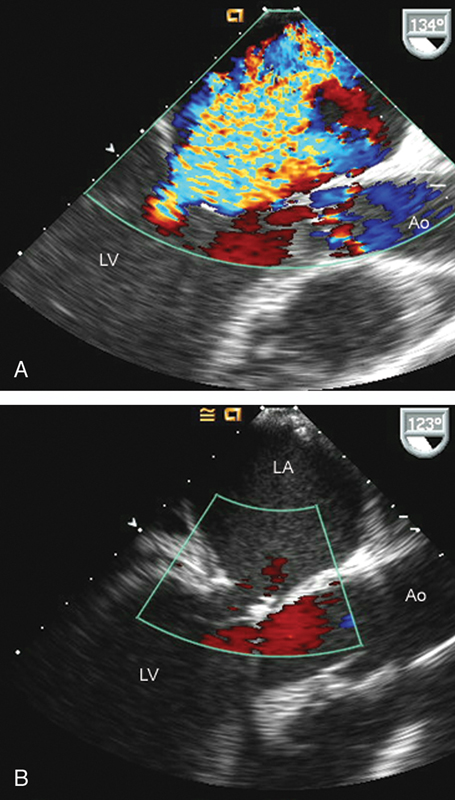

فحوصات تشخيصية لبعض امراض القلب والشرايين التاجية